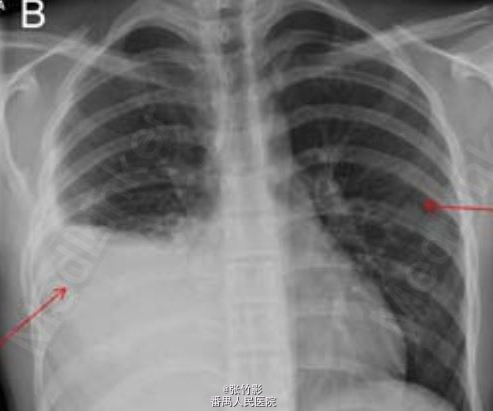

查体:右侧胸部叩诊浊音,呼吸音减弱;未问及明显干湿性啰音。 辅查:首次就诊血液学检查白细胞计数正常,C 反应蛋白升高(303 mg/L);两次胸部X线如下。

诊断:骨性肋外生骨疣引起血胸。 处理:患儿呼吸急促,需要吸氧 1-2L/min,同时对患者静脉用克拉维酸和克拉霉素。在超声介导下行右半胸腔穿刺引流,引流出 750 ml 深黑色的血性液体,而非脓液。

讨论:该病例旨在提醒医者们即使已经在胸片上发现明显的异常改变,仍应仔细查看胸片,在患儿初次就诊时就医者就忽略了外生骨疣这一改变。血胸常由胸部创伤引起,儿童少见。血胸也可因炎症发展如脓肿和结核侵袭血管所致。血胸偶可为胸部肿瘤、肋外生骨疣和出血体质的临床表现。自发性血胸可见于新生儿和年龄较大的儿童,但此种情况极为罕见(转自 Thorax 杂志)。